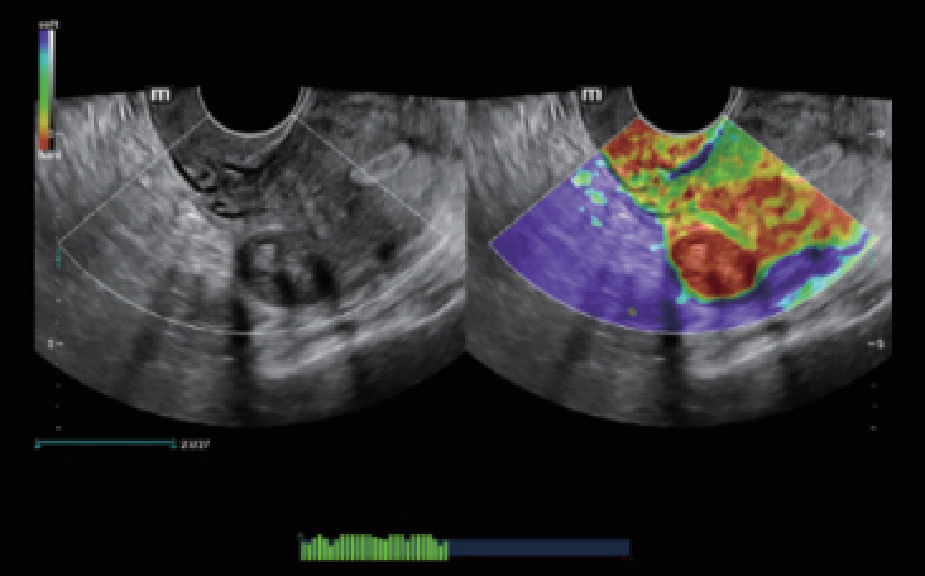

El sistema Nuewa I9, dise?ado exclusivamente para la atenciĂłn mĂ©dica neonatal y de mujeres, brinda una experiencia innovadora integral. Estas innovaciones se desarrollan sobre la base de un conocimiento profundo de situaciones clĂnicas complejas para proporcionar respuestas precisas y oportunas, una gran eficiencia y una experiencia de usuario extraordinaria.

SoluciĂłn completa con tecnologĂa de ZST +

La plataforma ZST+?es una innovaciĂłn extraordinaria que representa toda una evoluciĂłn en el ĂĄmbito de la ecografĂa. Transforma las mĂ©tricas ecogrĂĄficas de la formaciĂłn de haces convencional al procesamiento basado en datos de canal. Supera la limitaciĂłn tradicional de tener que equilibrar entre resoluciĂłn espacial, resoluciĂłn temporal y uniformidad del tejido, con lo que ofrece una calidad de imagen excepcional para soluciones de producciĂłn de imĂĄgenes infinitas con mejoras continuas.